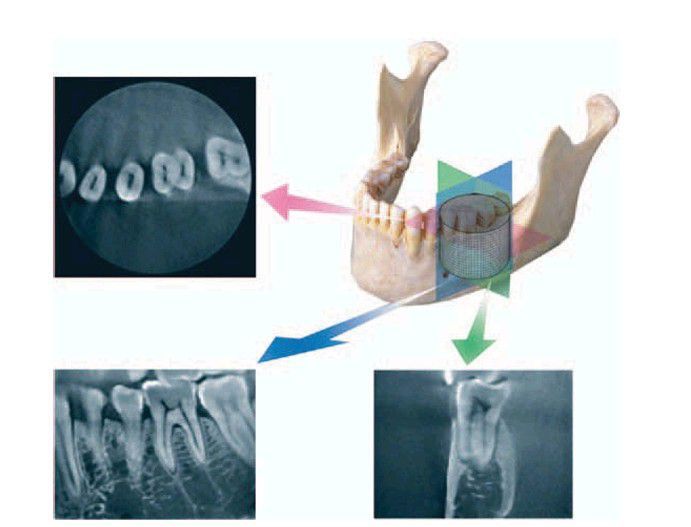

Cone-beam volumetric tomography has the advantage of being able to detect pathosis in the bone or associated with the teeth without the obstruction of anatomic structures. The planes of vision may be axial, sagittal,